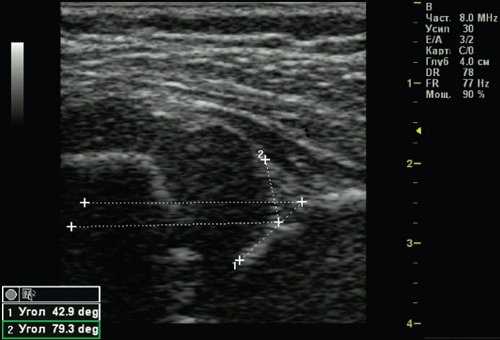

У 1 (0,25%) ребенка выявлен 3а тип тазобедренного сустава - врожденный вывих бедра (рис. 6). Костная часть вертлужной впадины и эркер плоские, хрящевая часть вертлужной впадины смещается краниально, так как головка бедра не может быть зафиксирована в вертлужной впадине, происходит ее децентрация. Структура хрящевой части крыши не изменена. Угол α меньше 43°.

Рис. 6. Тазобедренный сустав тип 3а.

1 - угол α=42,9°;

2 - угол β=79,3°.